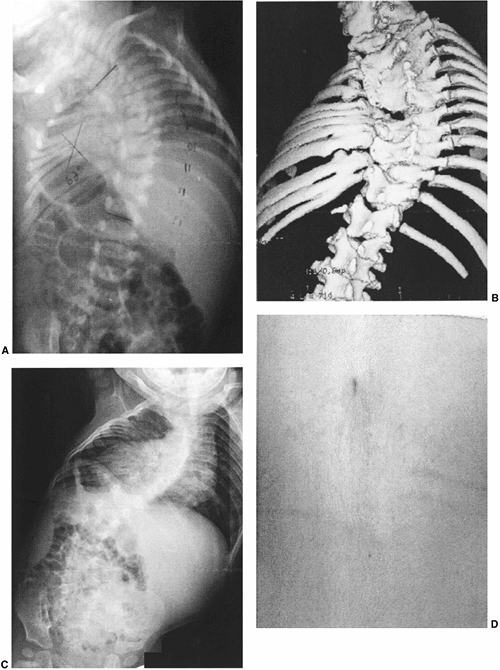

Figure 19.2 Anomalies associated with congenital scoliosis. A:

One-week-old infant with congenital scoliosis. The multiple vertebral anomalies seen here include vertebral bony bars, hemivertebrae, and wedge vertebrae. Other anomalies included ear anomalies and deafness, solitary kidney, imperforate anus, tethered spinal cord, atrial septal defect, hypoplastic lung, and radial hypoplasia. B: Three-dimensional computed tomography (CT) scan of the same patient at 10 months. Fused ribs on the concavity of the thoracic scoliosis will act as a tether, producing more deformity with growth. C: Upright radiograph at 10 months. A new curvature in the more normal thoracolumbar spine is compensatory to the upright position, but should suggest the possibility of spinal cord tethering. D: Cutaneous abnormalities such as this skin dimple over the thoracolumbar spine may indicate an underlying intraspinal anomaly. |